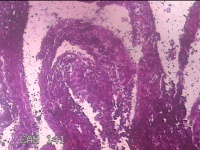

宫颈内容物

性别

女

年龄

29岁

临床诊断

异常子宫出血

一般病史

不规则阴道流血1个月余。

标本名称

大体所见

灰白暗红色不规则碎组织1.8x1.3x0.3cm一堆。

图1